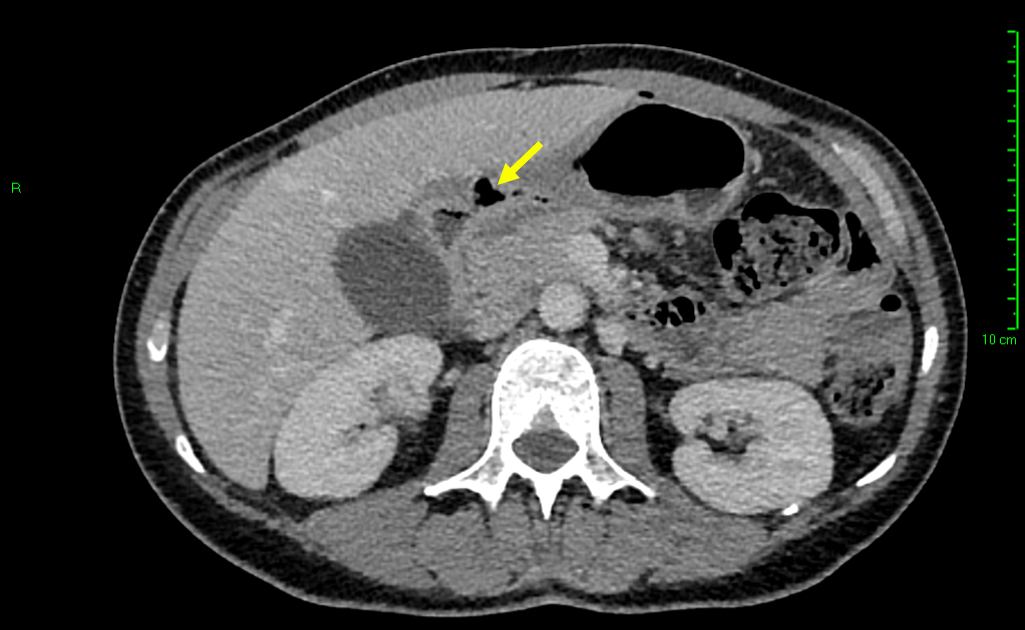

Sonographic examination demonstrated a full thickness mucosal defect of the anterior pre-pyloric region of the stomach, with extraluminal gas locules (see image), trace free fluid in the gallbladder fossa and complex fluid in the right iliac fossa. These features were consistent with a perforated pre-pyloric gastric ulcer. An urgent CT scan was arranged, which confirmed the diagnosis (see images). The patient subsequently underwent emergency laparoscopic surgery. The perforated ulcer, loosely sealed by omentum and the medial edge of the liver, was identified and repaired with an omental plug procedure. Further management included postoperative intravenous antibiotics and PPIs. The patient made a good recovery and was discharged four days post-operatively, with Helicobacter pylori eradication therapy and analgesia.